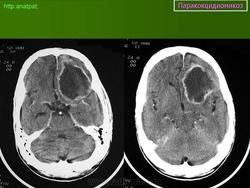

ГМ. Паракокцидиомикоз. +

Паракокцидиомикоз.

Множественные "узловые образования" имитирующие метастазы.